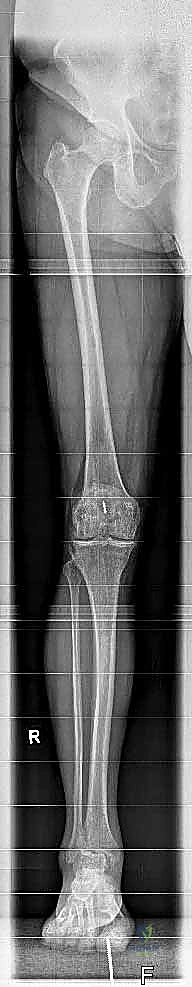

لفهم أهمية جراحة استبدال الكاحل، يجب أولاً فهم تشريح هذا المفصل المعقد. يتكون مفصل الكاحل من التقاء ثلاث عظام رئيسية:

1. عظمة الظنبوب (Tibia): وهي عظمة الساق الكبرى التي تشمل الجزء الداخلي والعلوي من الكاحل.

2. عظمة الشظية (Fibula): وهي عظمة الساق الصغرى التي تشكل الجزء الخارجي من الكاحل.

3. عظمة الكاحل (Talus): وهي العظمة السفلية التي ترتكز عليها عظام الساق وتعمل كمفصلة للحركة.

1. التقييم والتحضير قبل الجراحة

يتم إجراء فحوصات شاملة تشمل الأشعة السينية (X-rays)، والأشعة المقطعية (CT scan) لإنشاء نموذج ثلاثي الأبعاد لكاحل المريض. يساعد هذا د. هطيف في اختيار الحجم الدقيق للمفصل الصناعي وتحديد زوايا القطع بدقة متناهية.

3. إزالة الأسطح التالفة (تحضير العظام)

باستخدام أدوات جراحية دقيقة وموجهات خاصة، يتم إزالة الغضاريف التالفة وجزء رقيق جداً من العظام المريضة من نهايتي عظمة الظنبوب وعظمة الكاحل (Talus). يتم تشكيل العظام بدقة لتتطابق تماماً مع شكل أجزاء المفصل الصناعي.